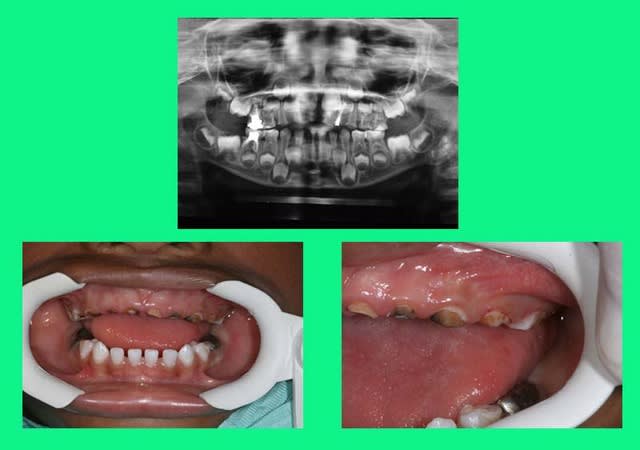

traitement global: ns aussi,en pedo,on peut!

à court terme,d'accord mais c'est mieux que rien(des dents de lait:les soigner? pourquoi faire?)

antoine: bientôt 5 ans

fin

pr les anterieures sup on verra en rentrant,radios à l'appui,et en fonction de la rhizalyse si ça vaut le coup de les remplacer

pr le moment: